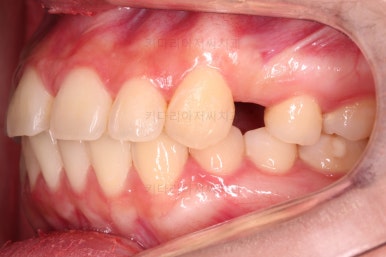

초진 시 입안의 모습을 보실게요.

결국은 앞니 사이에 틈이 생겼기 때문에 이같은 문제점을 인지하시고 내원하셨던거죠.

환자분 : "임플란트 하기 전에 앞니 틈도 모으고 싶어요."

이번 환자분의 경우는 치아 결손 부위의 잇몸뼈도 양호했고 공간도 그리 크진 않았으며 윗니는 갯수가 1개 부족해도 교합을 맞추는데 문제가 거의 없기 때문에 시간이 좀 더 들더라도 임플란트 없이 앞니 사이 틈과 결손부위 틈새를 모아보기로 했어요.